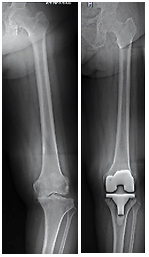

| Gambar 6: Pengapuran sendi berat disertai deformity (kaki O atau X), dilakukan total knee arthoplasty (TKA) untuk mengkoreksi deformitas dan mengurangi nyeri. |